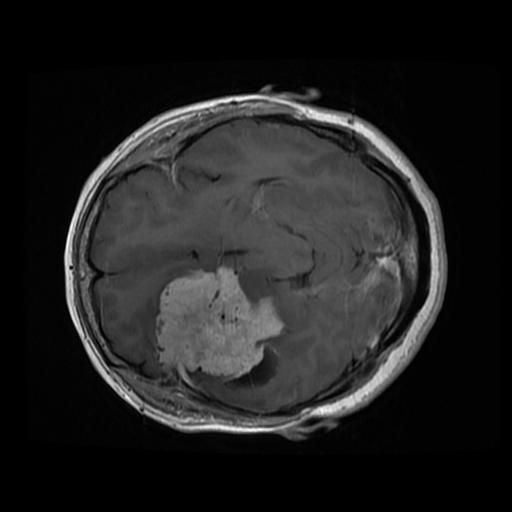

Screenshots